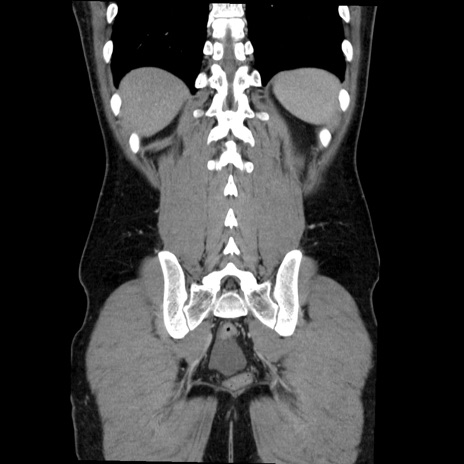

症例36(冠状断像)

【症例】20歳代 男性

【主訴】心窩部痛

【現病歴】今朝より上腹部痛あり。一旦軽快していたが再度出現したため救急要請。昨日夕に白身の魚を含む刺身を食べた。

【身体所見】BP 136/89mmHg、HR 74/min、BT 37.0℃、腹部:膨満、軟、心窩部に圧痛あり。反跳痛なし、筋性防御なし、腸雑音やや亢進あり。

【データ】WBC 17700、CRP 0.48